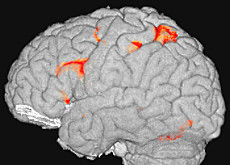

ボサー : まず脳造影法や機能的磁気共鳴影像法 ( fMRI ) などによって脳をスキャンします。またマウスを使う研究も行います。つまり、マウスを金融リスクに似たある種のリスク状態に置き、検査します。これの良い点は、脳全体が機能しない状態で特に神経を研究できることです。

実際のところ、金融界のリスクは非常に特殊なリスクです。一番予想不可能なリスクといえるかもしれません。株式会社の形態ができた15世紀以来、我々の脳はまだそれに適応できずにいるのです。ニューロ・ファイナンスは従ってリスクの多い金融界でどのように選択がなされているのかを解明しようとしています。脳の機能に取り組み、感情を大切な要素に考えています。